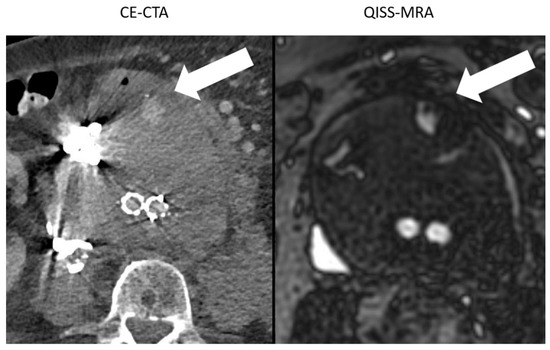

4.3. Visualization of Endoleaks and Image Quality